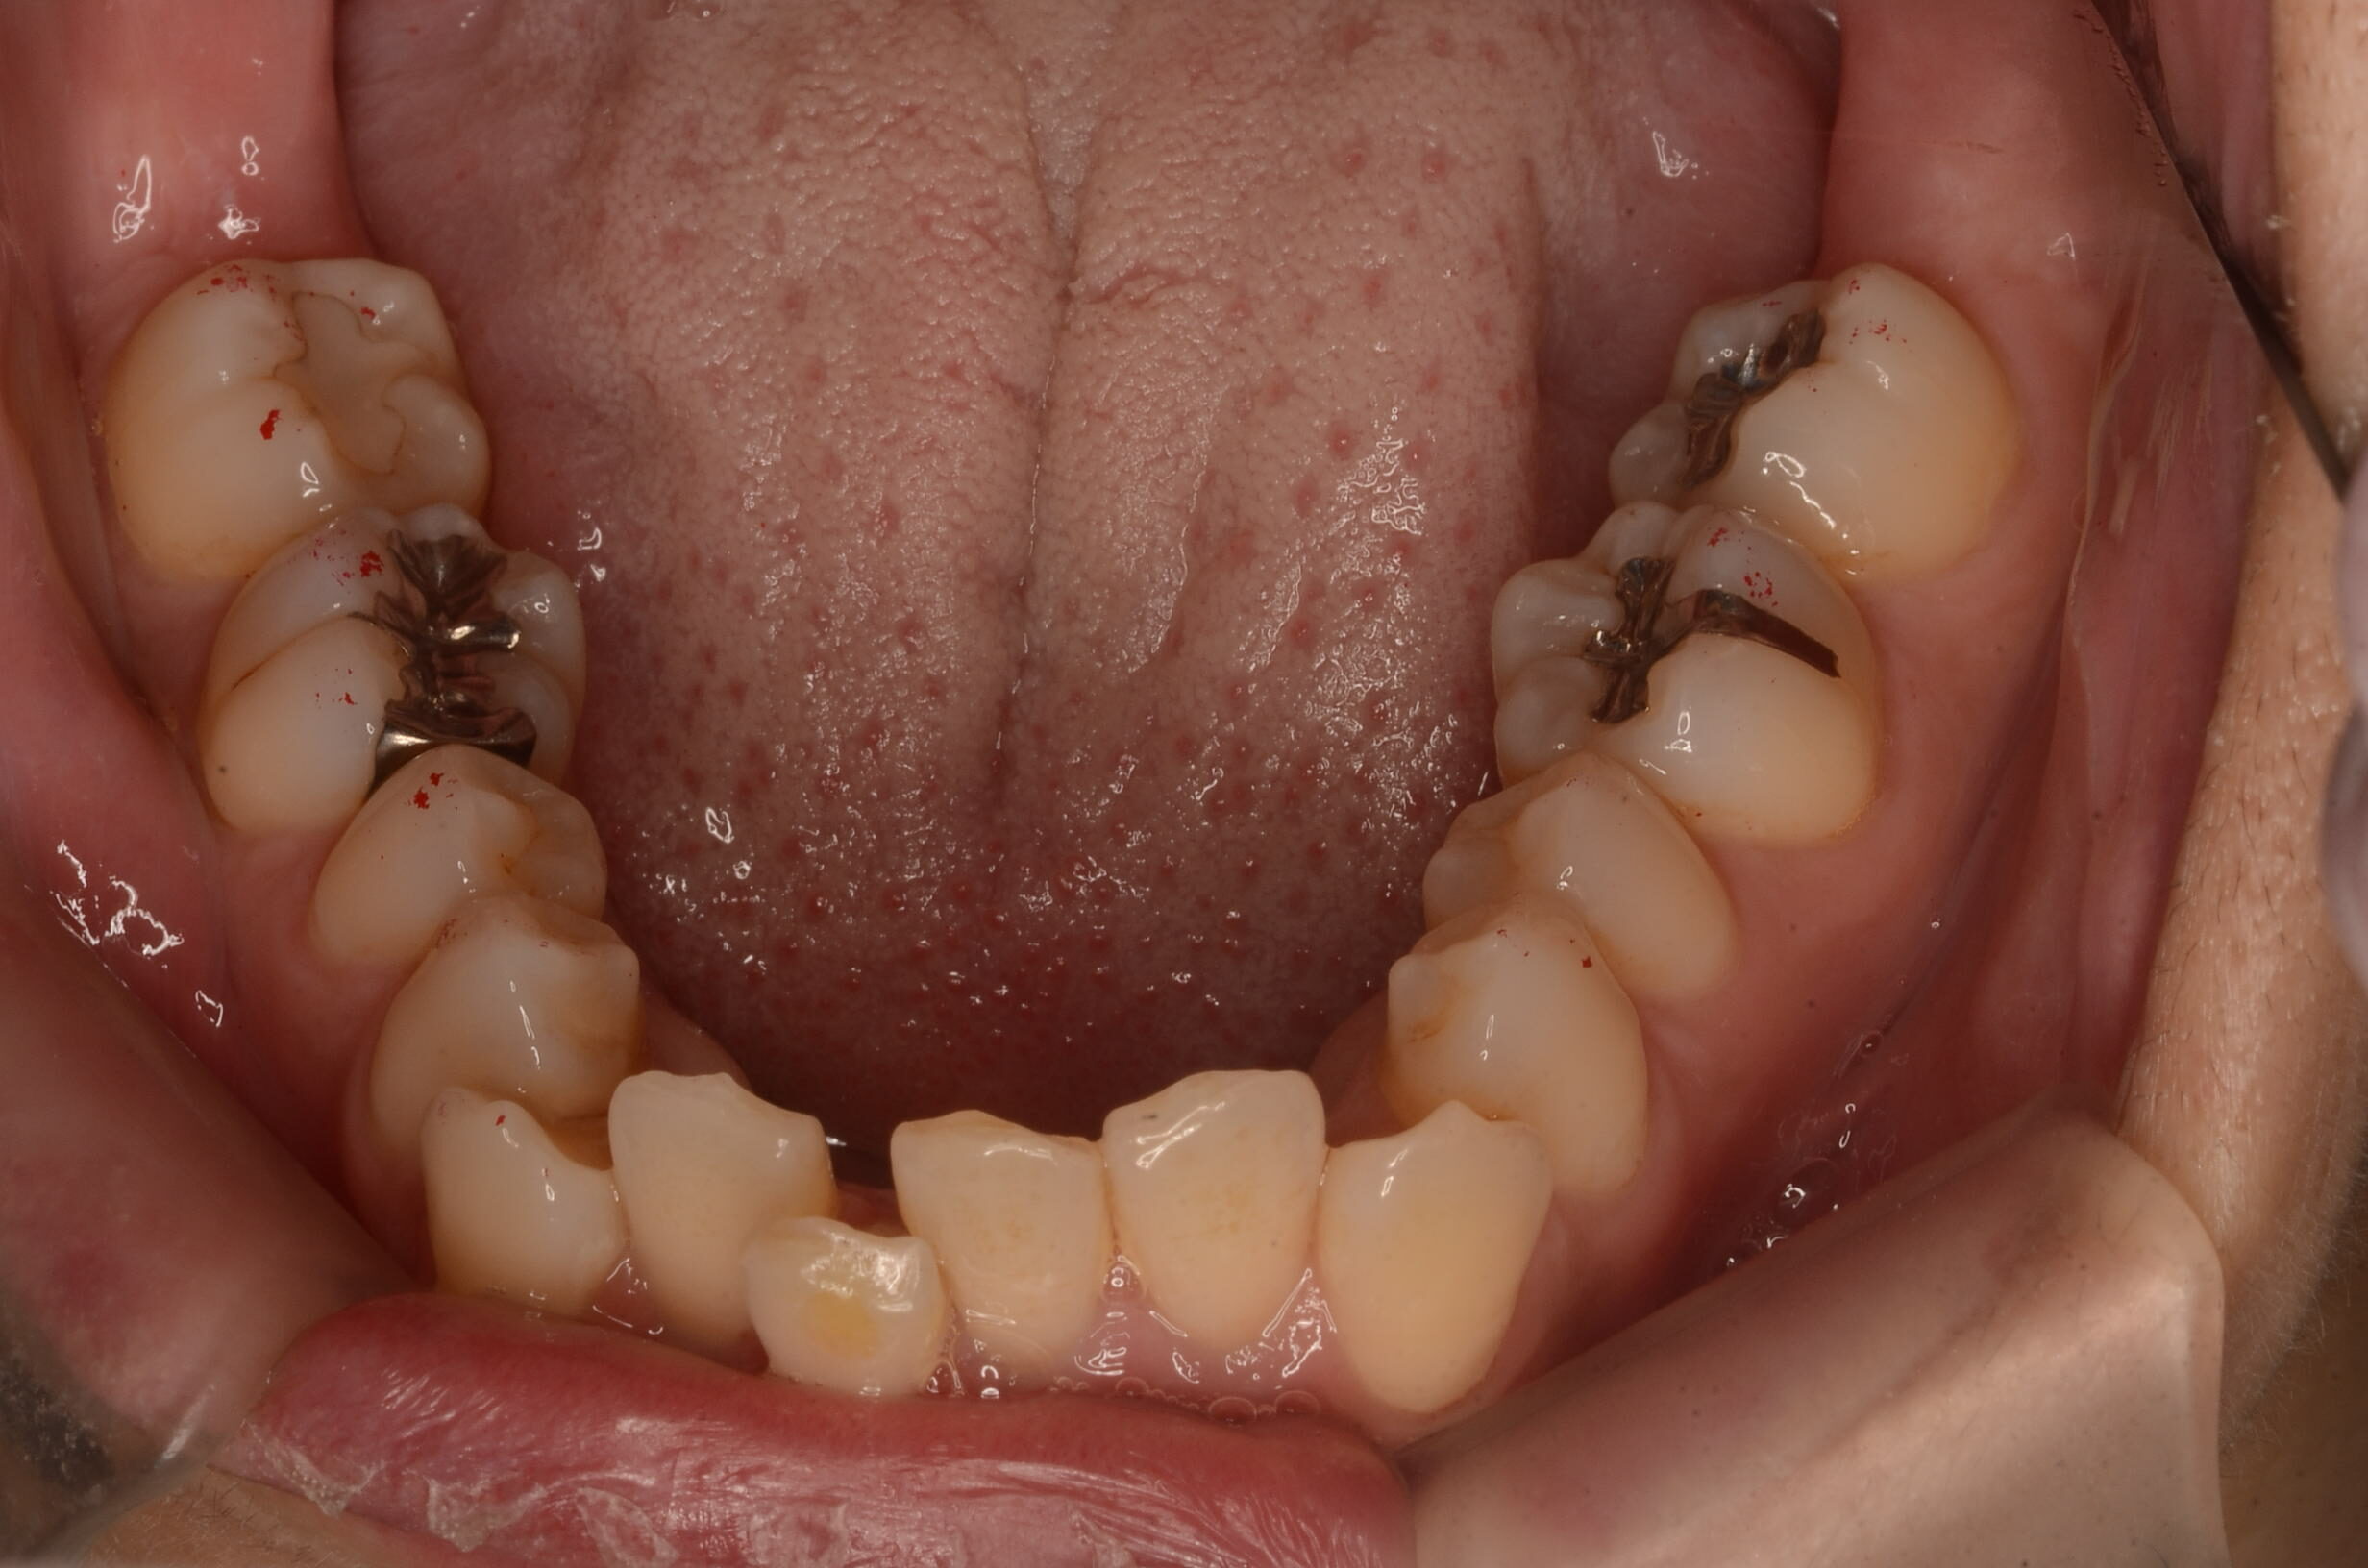

治療前_下顎咬合面

| 治療内容 | 患者様は、上顎前歯の突出や歯列の叢生(ガタつき)、笑った際に歯ぐきが見えすぎること(ガミースマイル)を主訴に来院されました。 診査の結果、抜歯を行うと歯軸の傾斜や歯列の陥没が懸念されたため、非抜歯でのインビザライン治療を計画しました。 |

- ・矯正治療中はプラークコントロール(PC)が不良になりやすく、う蝕(虫歯)や歯肉炎のリスクが高まります。 ・治療期間中はTBI(歯磨き指導)を適宜実施し、口腔衛生状態の改善を図りました。 ・アライナーの装着時間が不足すると、歯の移動精度や治療期間に影響を及ぼす可能性があります。 ・IPR処置部位では一時的に知覚過敏を生じることがあります。